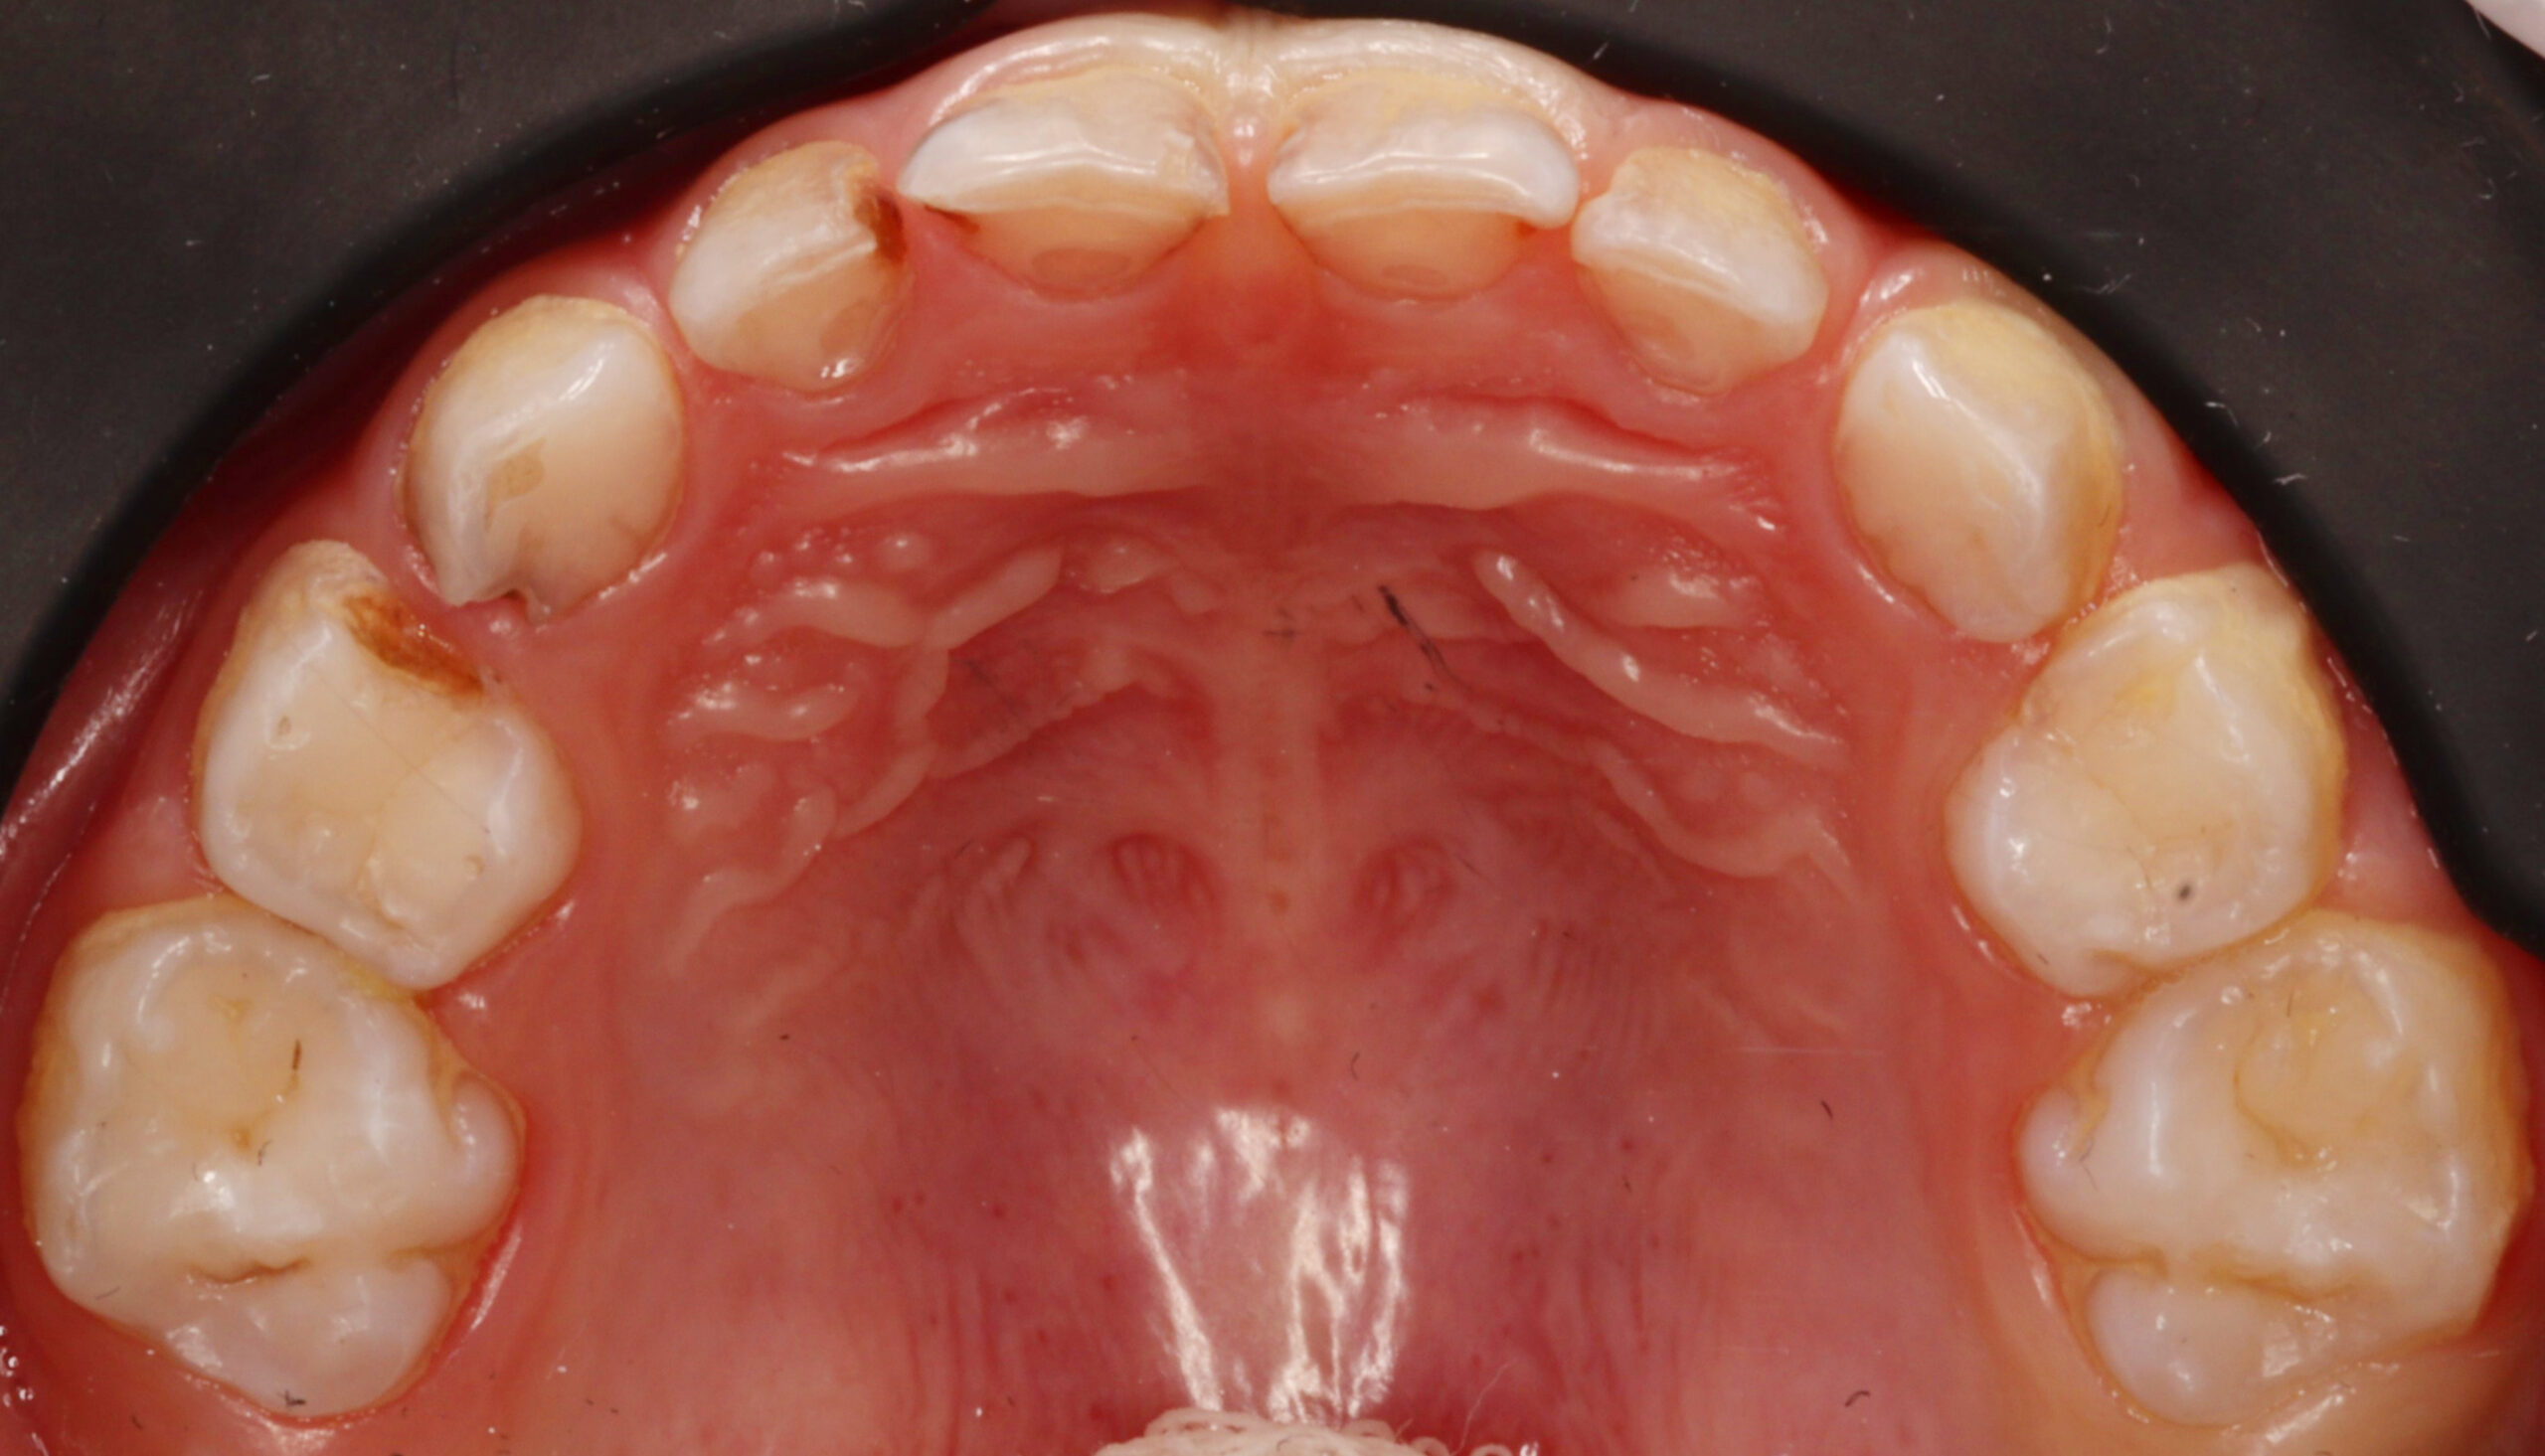

Специализация: лечение кариеса, пульпита и периодонтита временных зубов, эстетическая реставрация и профилактика